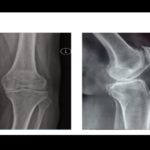

Medial Compartment OA Knee: HTO Vs Uni Vs TKA

Courtesy: Krishnakiran Eachampatti, Sachin Tapasvi and Panelists